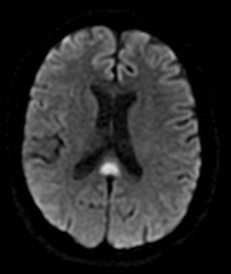

Qual a melhor sequência de RM para avaliar isquemia aguda?

DWI. Sensibilidade muito superior à TC (90 - 100%).